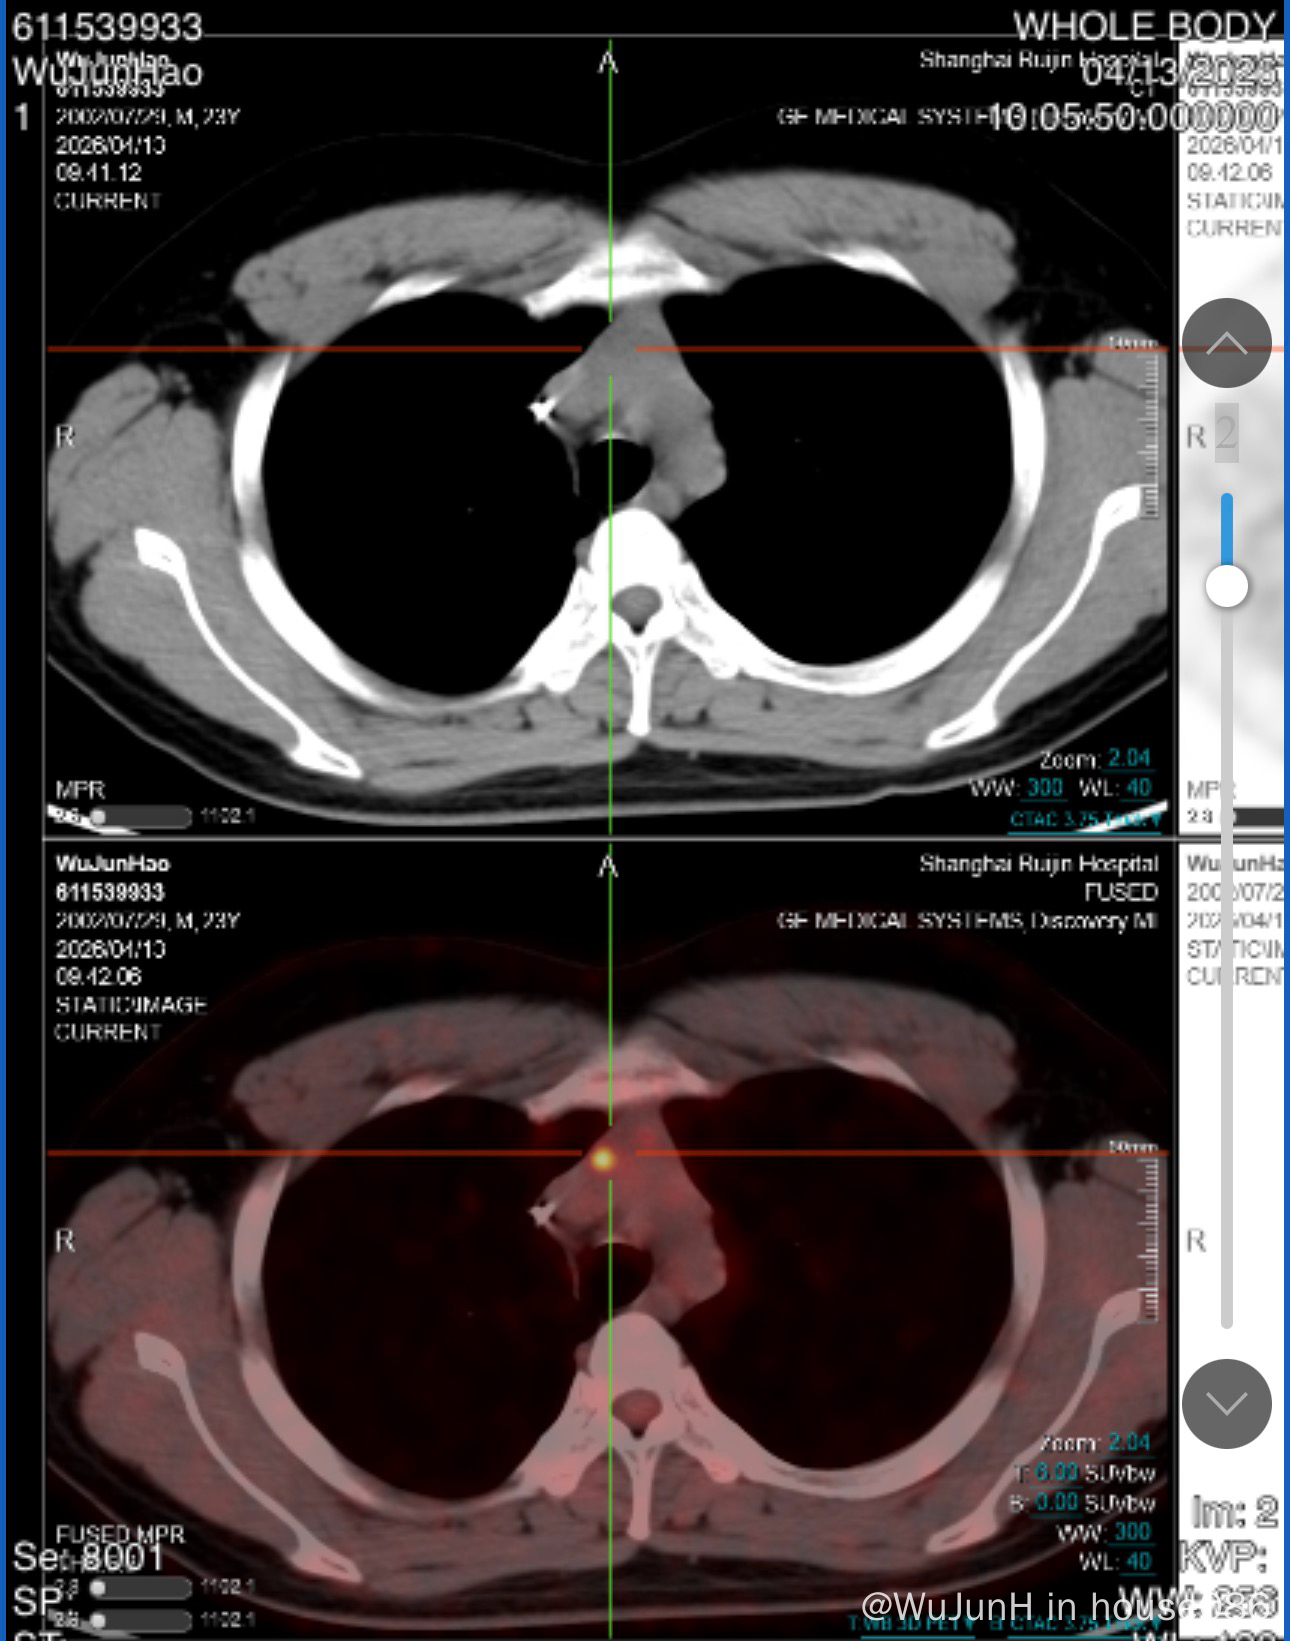

男23岁,发现时为四期,病灶大小是11*9cm,全身多处结外有受累,在瑞金r-da-edoch方案六个疗程,中期pet评估4分pr,但只剩下纵隔有活性suvmax4.4病灶大小3.6*1.9cm,主治说治疗有效继续原方案剂量治疗。末期评估还是4分,病灶小了一些达到2.0*1.5cm,但纵隔病灶suvmax达到6.8。由于病灶太小无法穿刺,没法确定是假阳还是肿瘤仍然具有活性,

现瑞金给的方案是直接放疗巩固,两个月后再做pet评估。放射科大夫说建议自体移植后再放疗或者cart,同情况病友说杨清明教授对于这种情况是先pd1治疗后cr再做放疗,认为如果肿瘤仍具有活性直接放疗可能会导致肿瘤扩散,导致病情进展。